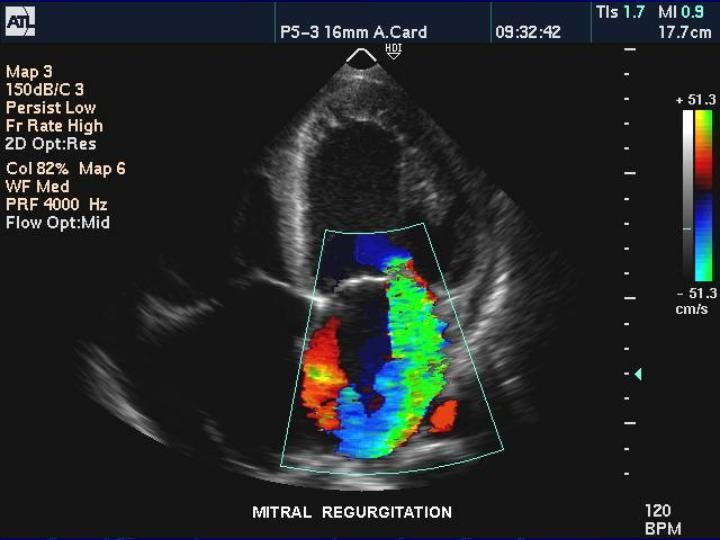

Ultrasound Imaging